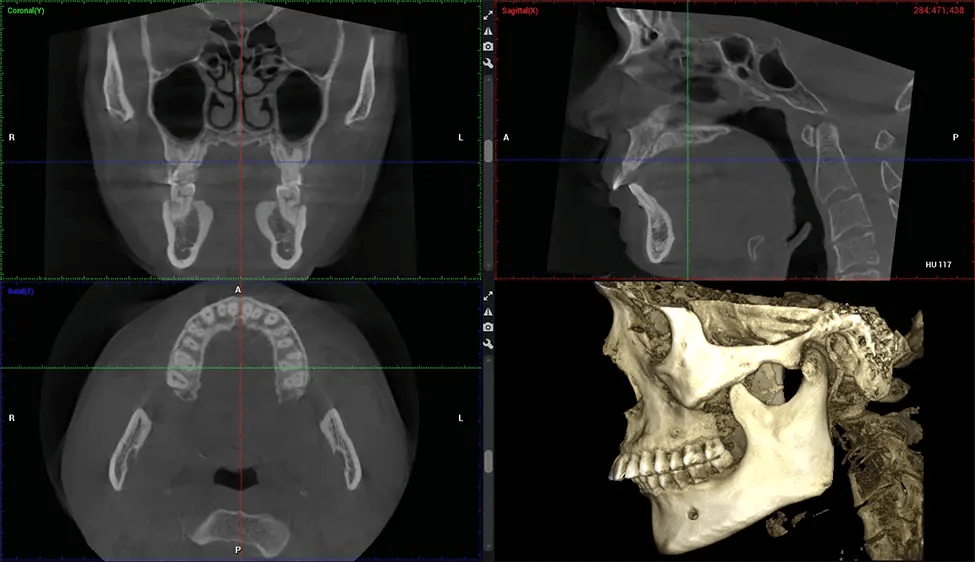

This 3D scan, called cone beam computed tomography, gives your dentist a more complete image of your oral anatomy and disease processes than a traditional X-ray. Unlike conventional X-rays, which capture a 2D image of your mouth from various angles, a 3D scan takes multiple digital X-rays for one image. It provides a complete view of your jaw, teeth, nerves, and soft tissues. This enhanced view allows dentists to detect minor issues not visible in traditional 2D scans, such as impacted wisdom teeth or bone fractures in the sinus cavity.

There are many benefits to using CBCT technology, especially compared to the traditional 2D X-ray format. One of the most significant advantages of CBCT scans is that they provide much more information than traditional X-rays. A scan lets your dentist see images from all angles of your jaw and mouth, including your sinuses, nasal cavity, cheekbones, and other surrounding areas. This added information helps your dentist craft a comprehensive treatment plan that addresses all aspects of your oral health.

Another significant benefit is that 3D imaging provides more precise images of your bone structure. These images are more detailed, providing you with a more accurate diagnosis. An accurate diagnosis means better treatment for you.